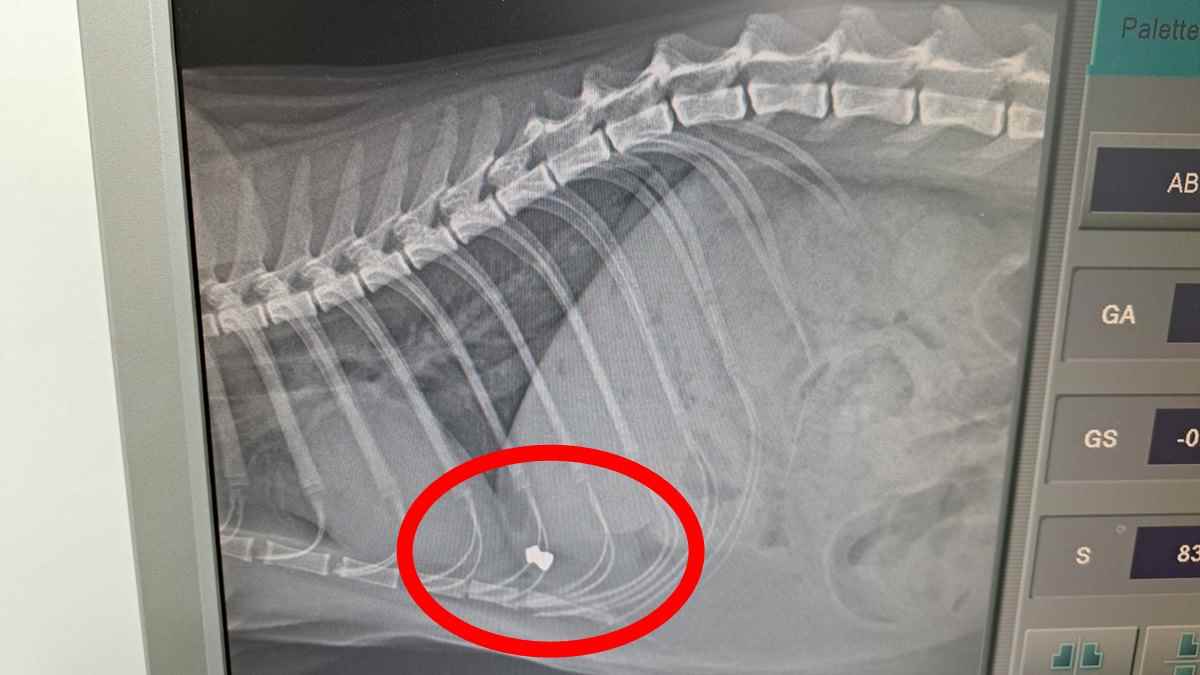

Αρχικά, η οικογένειά του νόμιζε ότι ο γάτος είχε παγιδευτεί κάπου, καθώς ήταν εξαντλημένος και καλυμμένος με κόλλες. Ωστόσο, η αλήθεια αποδείχθηκε πολύ πιο εφιαλτική, καθώς η ακτινογραφία αποκάλυψε ότι το ζώο είχε πυροβοληθεί με αεροβόλο όπλο.

Σύμφωνα με την ανάλυση των τραυμάτων του, το αεροβόλο είτε είχε εξαιρετικά υψηλή ισχύ είτε χρησιμοποιήθηκε από πολύ κοντινή απόσταση, καθώς η μεταλλική σφαίρα διαπέρασε ολόκληρο το σώμα του και σταμάτησε στην αντίθετη πλευρά.

Ο γάτος σώθηκε από καθαρή τύχη, αφού η σφαίρα δεν έπληξε κάποιο ζωτικό όργανο.